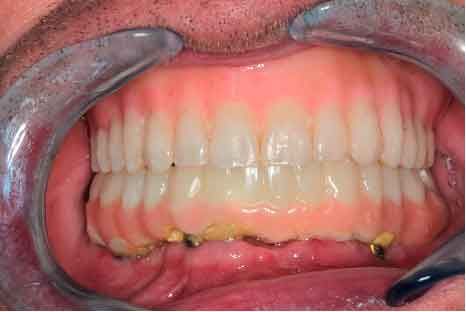

Une fois que les mouvements de la mâchoire du patient sont enregistrés, le logiciel TWIM est une aide supplémentaire pour le diagnostic et la planification du traitement.

étape 4 - EXPORT DES DONNées vers le laboratoire

Lors du premier rendez-vous, la collecte de données complète est essentielle. Des photos aux fichiers DICOM segmentés et aux données de mouvement de la mâchoire, toutes les informations sont intégrées dans le logiciel TWIM, simplifiant la communication avec le laboratoire dentaire.

L'ensemble des données est envoyé au laboratoire pour concevoir les provisoires.

• Flux de travail numérique : Passez de la situation initiale aux provisoires en utilisant les données du patient, dans un flux de travail numérique.

• Flux de travail simplifié : En éliminant le besoin d'empreintes physiques et cires d'occlusion, ce flux de travail réduit le temps et les ressources nécessaires

• Expérience patient améliorée : Les patients bénéficient d'une esthétique améliorée et d'un confort fonctionnel accru tout au long de leur parcours de traitement.